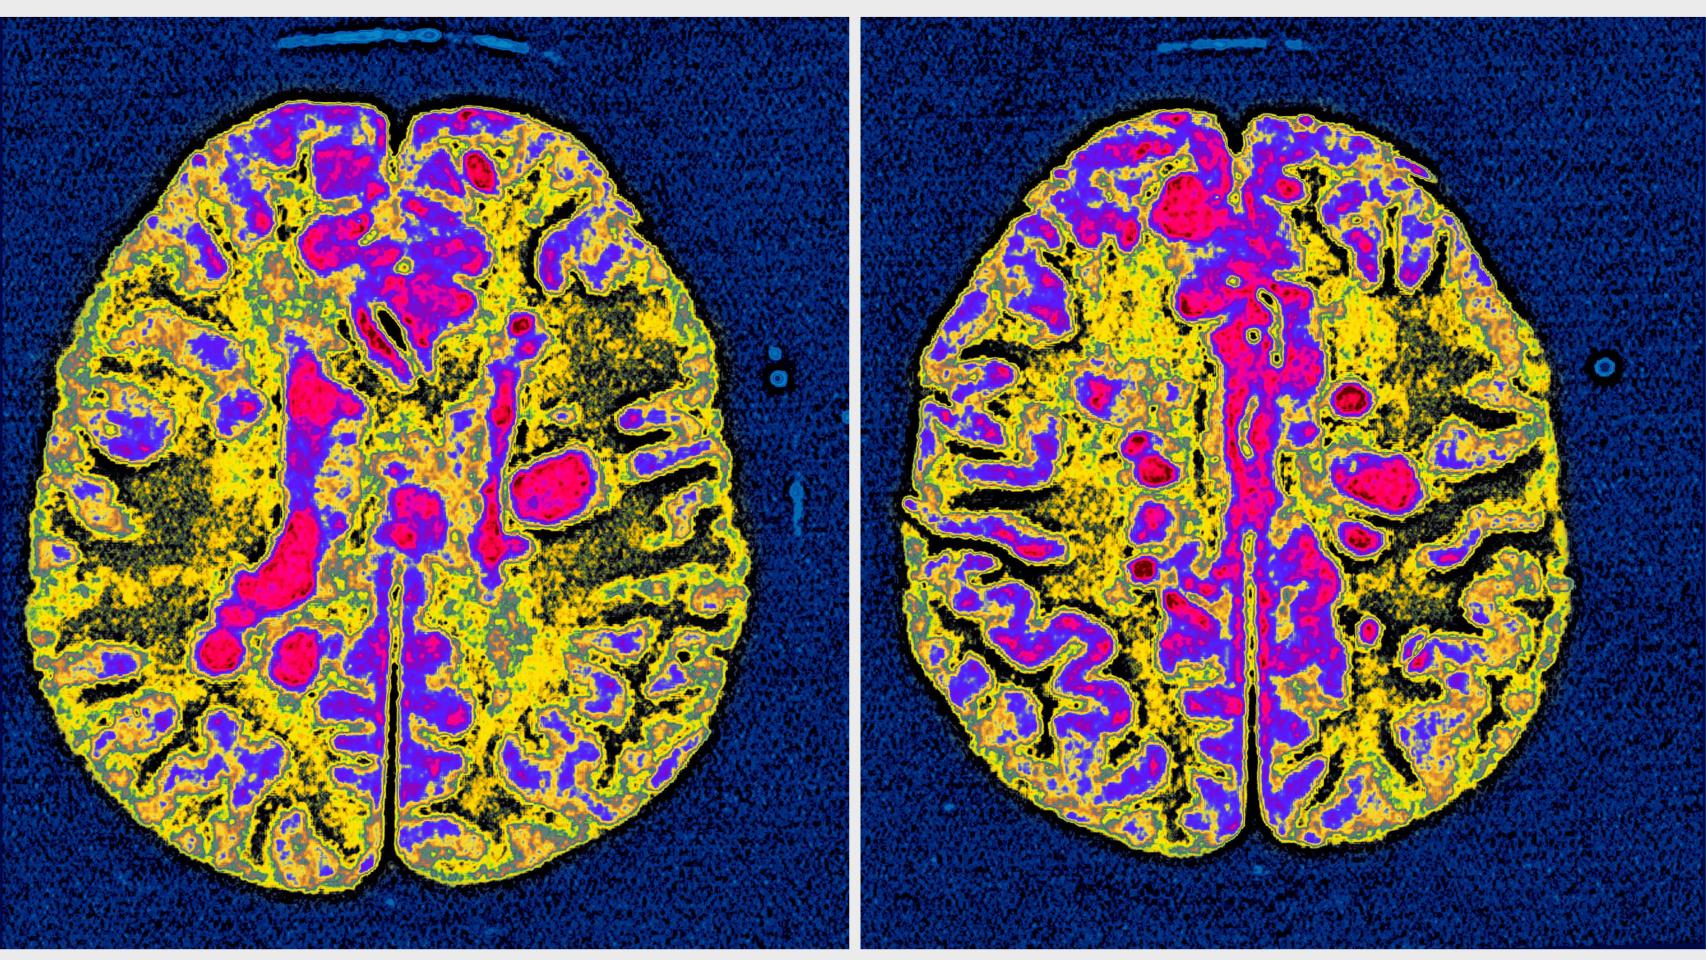

Una resonancia de un cerebro afectado por esclerosis múltiple. Getty Images